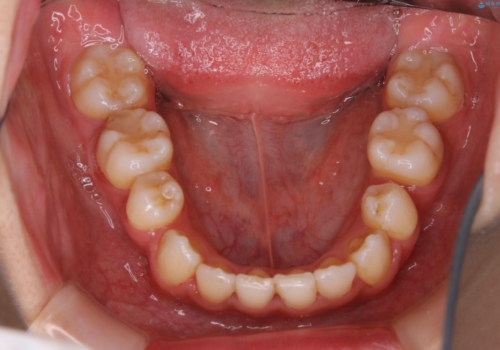

- 元々は海外でワイヤー矯正を行っていたが、コロナ禍で海外への往来が難しくなり、治療を中断せざるを得なくなってしまった方です。

ご本人のご希望により、インビザラインによる治療を行いました。

ブラケット除去直後に目立っていた下顎前歯部の大きなブラックトライアングルもあまり目立たなくなり、大変喜んでいただけました。